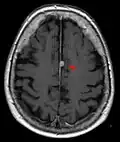

Brain regions on T1 MRI

T1 (note CSF is dark) with contrast (arrow pointing to meningioma of the falx)